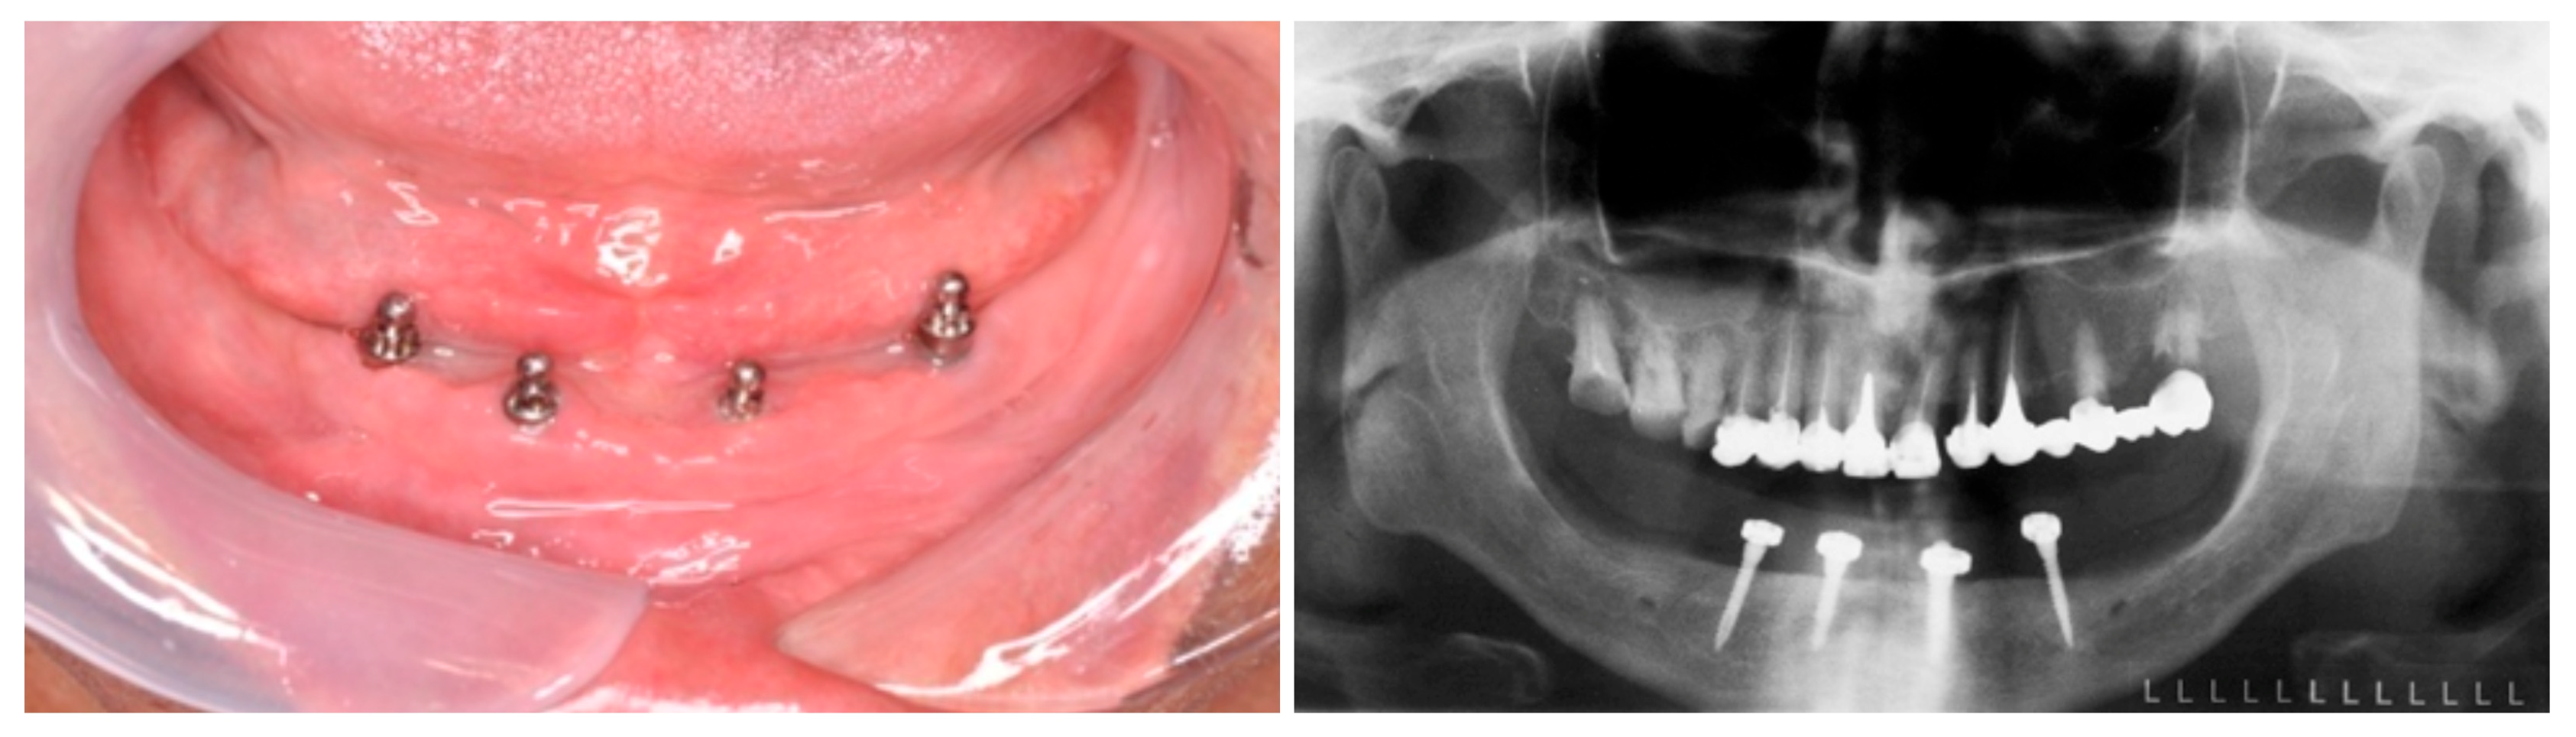

2.1. Clinical and Radiological Examination